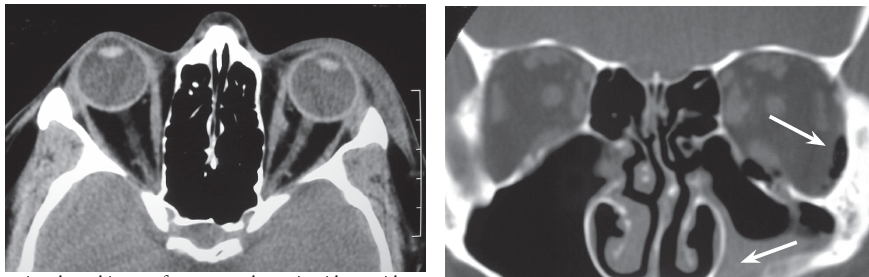

Laboratory testing. An upright radiograph revealed fluid in the left maxillary sinus consistent with hemorrhage. Orbital floor fracture was diagnosed. An axial CT scan of the orbits demonstrated widening and increased density in the periorbital fat, which indicated soft tissue swelling.

The scan was performed to evaluate the medial and lateral walls of the orbit, which were determined to be intact. A direct coronal CT scan showed the depressed fracture of the orbit floor, hemorrhagic debris in the left maxillary sinus, and intraorbital emphysema; air was noted passing through the fracture from the left maxillary sinus into the left orbit. Coronal imaging is best for visualizing the roof and floor of the orbit. If direct coronal imaging cannot be performed, thin-section axial images can be obtained with generation of coronal reformats.

Discussion. Orbital floor fractures may be caused by direct trauma to the inferior orbital rim, which results in buckling of the orbital floor. Fractures may also occur when rapidly increased intraorbital pressure is decompressed at the weakest point of the bony confines of the orbit. Suspect an orbital fracture when a patient has a history of trauma, ecchymosis with or without edema of the lids, diplopia, hypoesthesia of the cheek (related to injury to the infraorbital nerve), or emphysema of the orbit or lids. Enophthalmos and ptosis of the globe indicate a large fracture. Fractures of the orbit frequently involve the weakest part of the bony orbit—the lamina papyracea or medial wall. If the medial wall is involved, hemorrhagic debris is seen in the ethmoid complex, and air that emanates from the ethmoid results in intraorbital emphysema.